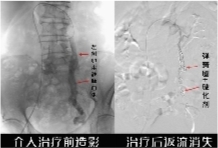

• 治疗前后对比。通讯员供图

株洲市三三一医院介入放射科主任章旭团队为她进行了精准的血管造影检查,果然发现左侧卵巢静脉明显增粗、迂曲。随即,团队为她实施了微创介入治疗——用弹簧圈+硬化剂联合栓塞的方式,解决了这根“问题血管”。

造影复查显示,淤血消失了。术后第二天,刘女士的疼痛评分就从7分(重度)降到了2分(轻微)。半年过去,她终于摆脱了多年的疼痛困扰,生活回归轻松。